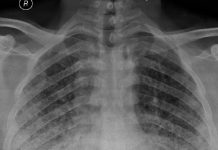

Eğer bir intratorasik opasite herhangi bir yapı ile anatomik kontakt halinde ise onun sınırlarını siler. Akciğer grafisinde bu lokalize opasitenin; kalbin mediastenin veya diafragmanın kenarlarını kısmen silmesi veya tamamen maskelemesine silüet bulgusu denir. Grafide sağ akciğerde orta zonda oluşan pnomoniye bağlı konsolidasyon sağ kalp gölsenini belirsiz hale getirmiş ve silüet bulgusu ortaya çıkmıştır.